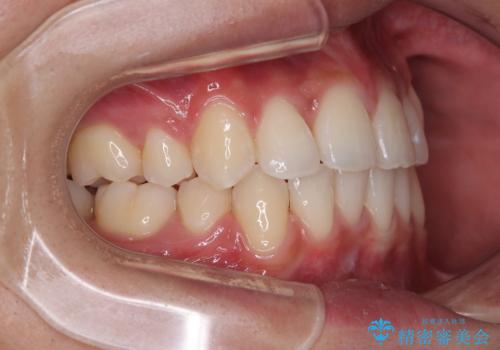

患者様の望んでいた通りの歯列や口元に仕上げることができました。